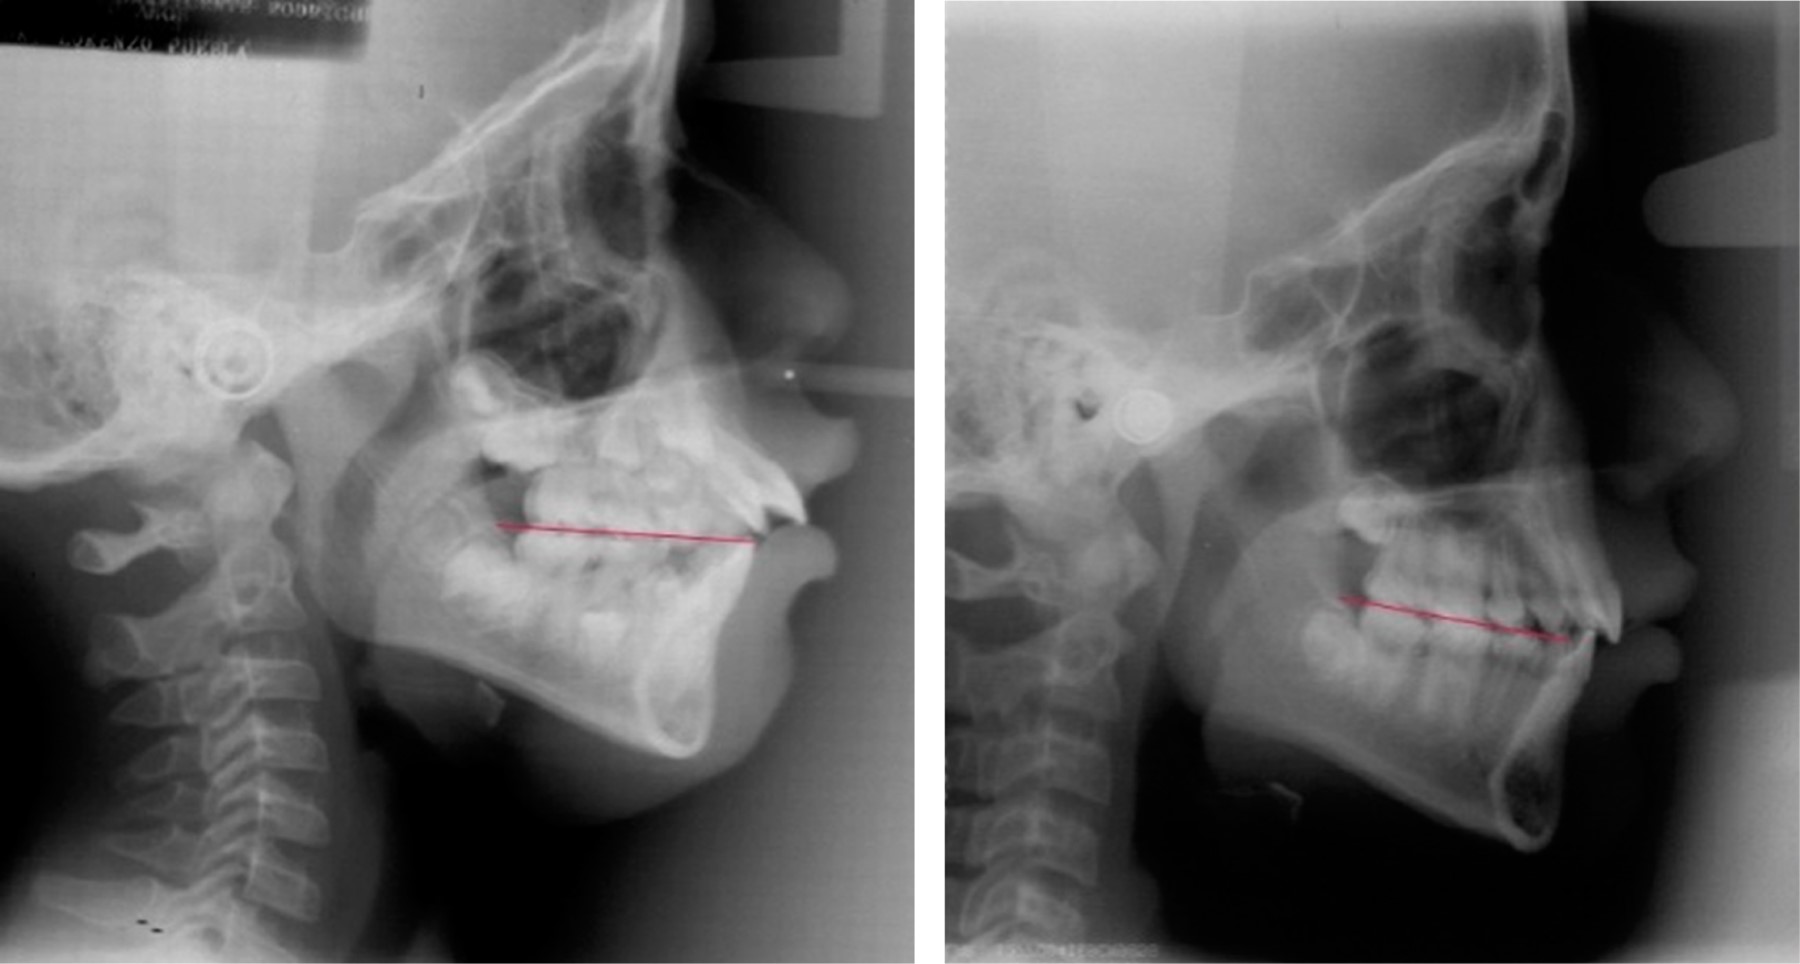

Por lo general, las áreas de mayor fuerza oclusal y de mayor área de contacto oclusal es en el lado hacia donde se desvía la mandíbula y hacia donde está inclinado el plano oclusal. Cabe destacar que no necesariamente es el lado donde predomina la sintomatología de las articulaciones (Figuras 4 y 5).11,12,18,19,21

Figura 4

Figura 5